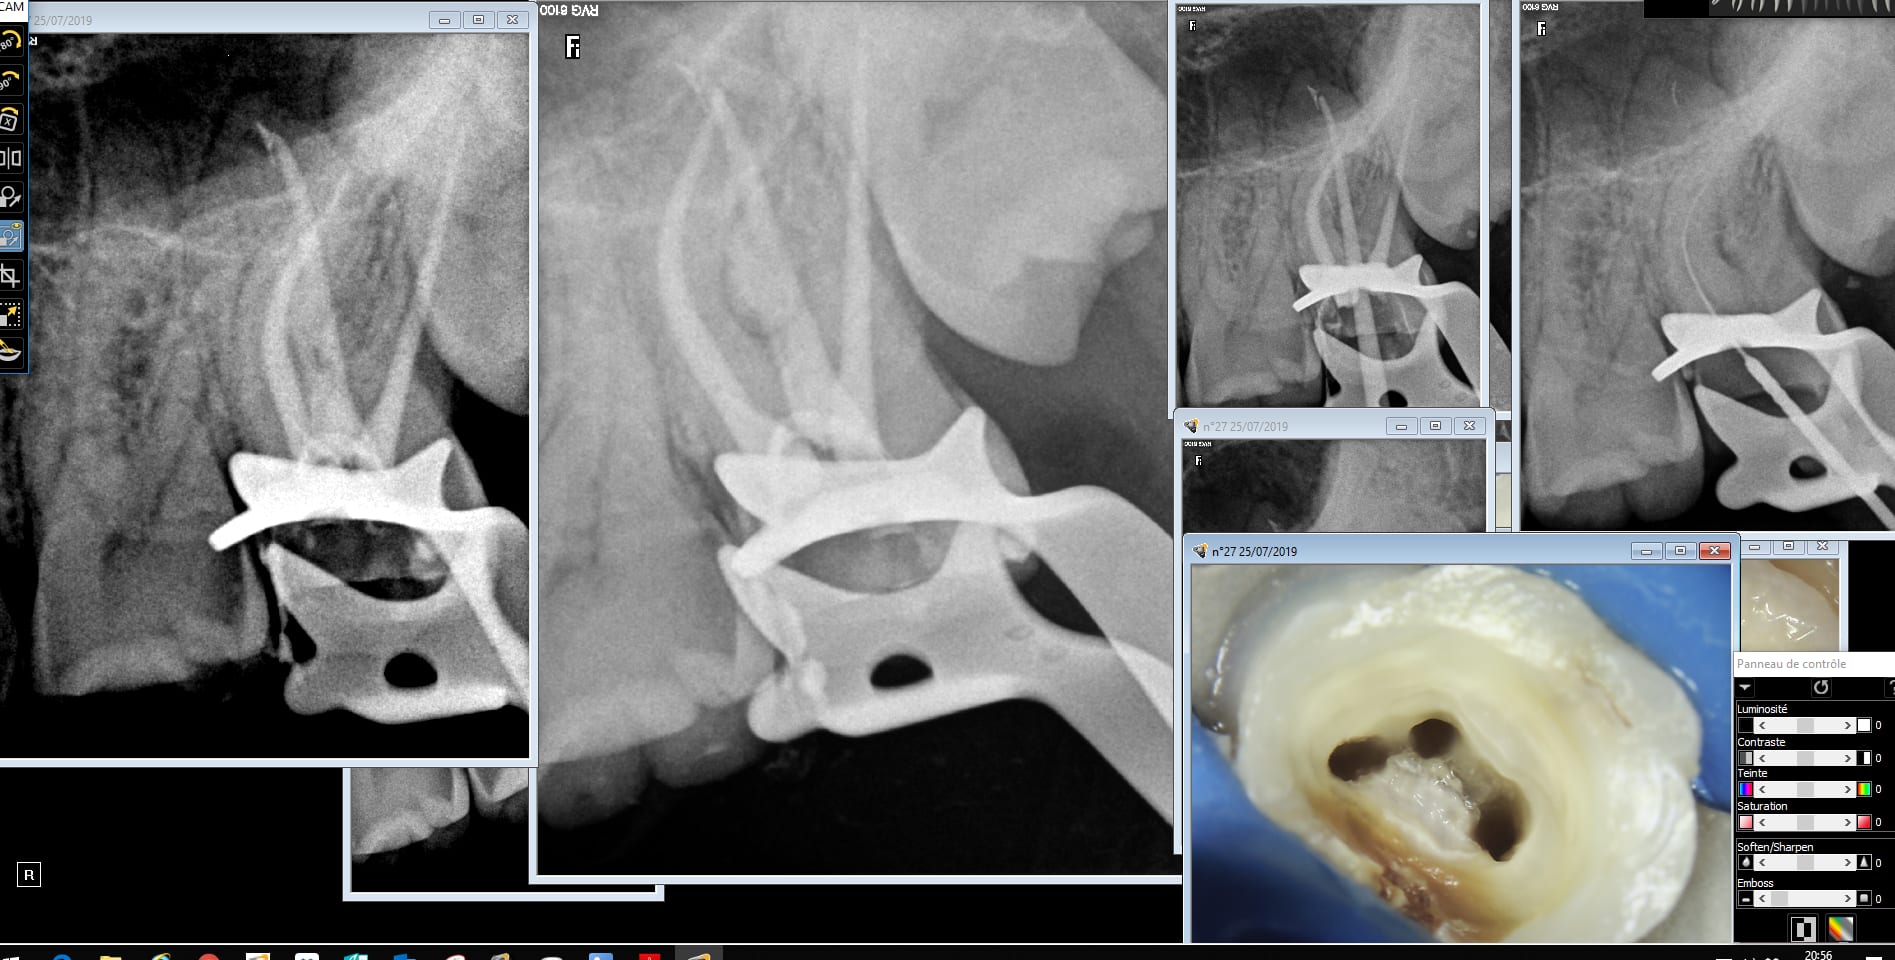

Ah merde. Je suis tombé sur un os. Vous reviendrez me dire bonjour en septembre bleu bite de l'endo. -)))

Racine palatine disons spéciale.